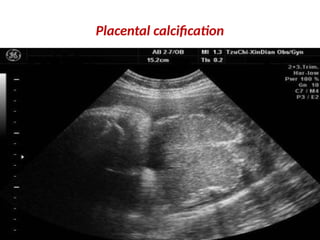

Placental calcification

Placental Aging. Thisplacenta (P) shows normal changes associated with advancing gestational age. The aging placenta develops hypoechoic areas (large arrow), septations (small arrows), and calcifications along the septations and placental surface. FH, fetal head